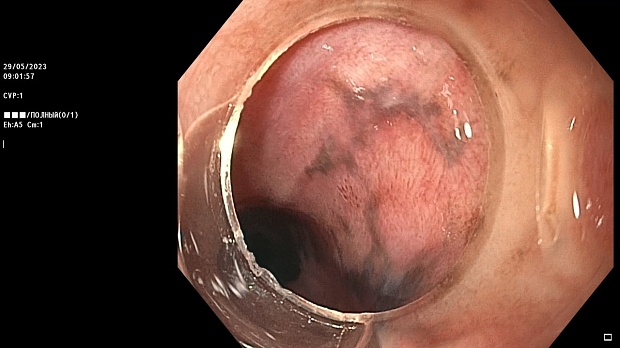

Иллюстрация №3: Эндофото. Сидероз нижней трети пищевода, эндоскопическая ультрасонография

Согласно полученным данным - в среднегрудном и нижнегрудном отделах пищевода определялась проксимальная граница плоских неправильной формы поверхностных рубцов суммарной протяженностью до 8,0 см. На этом фоне в зонах поверхностных рубцов по задней полуокружности визуализировались участки гиперпигментации в темный цвет (Рис. 1). При исследовании в режиме Dual Focus было отмечено наличие мелких (до 0,001 см) черно-коричневых включений, расположенных субэпителиально - в строме слизистой оболочки, сливания их в единый конгломерат не определялось (Рис. 2). При эндосонографии с применением минидатчика с частотой сканирования 20МГц выявлено, что все слои стенки четко дифференцируются, не утолщены, в слизистой оболочки визуализированы мелких гиперэхогенные включения с эхотенями (Рис. 3).

Протокол ЭГДС

В пищеводе в шейном его отделе на уровне 16 см от резцов циркулярно визуализированы единичные синюшные флебоэктазии размерами до 0.5 см. Дистальнее пищевод визуально не изменен до уровня 28 см от резцов, где определяется проксимальная граница плоских неправильной формы поверхностных рубцов, распространяющихся до уровня 36 см от резцов. На этом фоне в зонах поверхностных рубцов по задней полуокружности визуализированы участки гиперпигментации в черно-коричнеый цвет. При осмотре в режиме Near Focus с увеличением - между зон пигментации определяются расширенные капилляры типа II по Inoue-классификации. При биопсии отмечена десквамация плоского эпителия, визуализированы мелкие черно-коричневые включения в строме слизистой оболочки, размеры их до 0,001 см, сливания их в единый конгломерат не отмечается. При эндосонографии с датчиком 20Мгц в исследуемой зоне в слизистой оболочке определяются гиперэхогенные включения, в то время как в подслизистом слое - зоны со сниженной эхогенностью. При биопсии отмечается уплотнение ткани, однако истинной фрагментации не определяется. Уровень Z-линии совпадает с уровнем анатомического кардиоэзофагеального перехода. Розетка кардии эластичная, смыкается не полностью, расположена на уровне пищеводного отверстия диафрагмы.